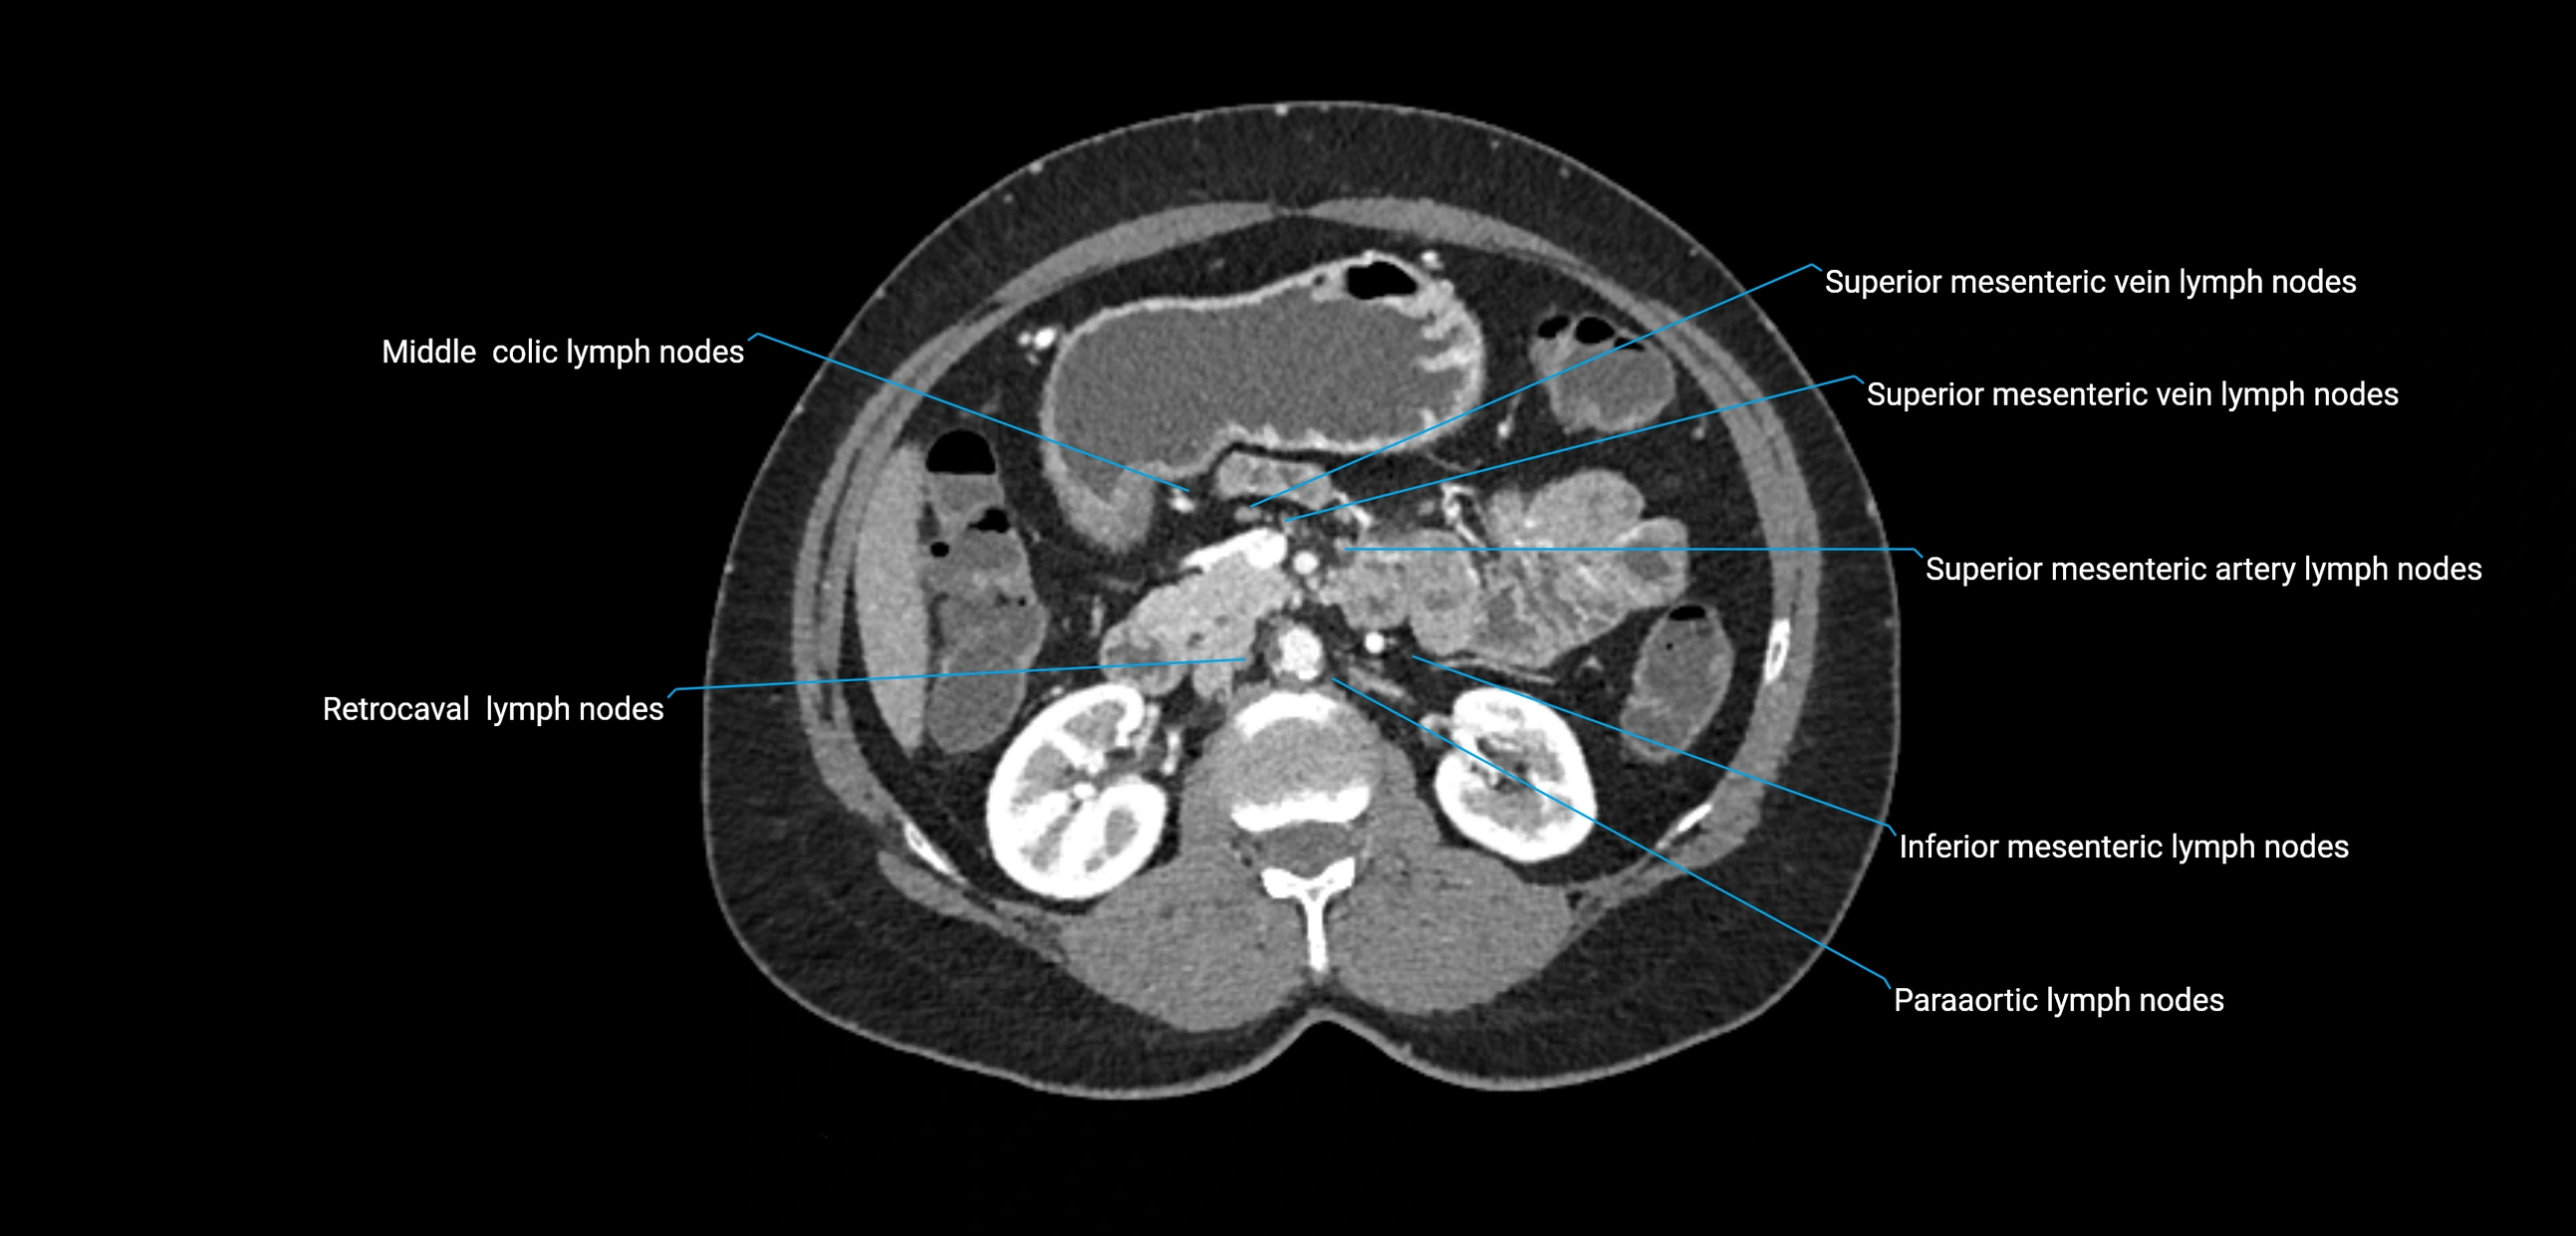

CT Appearance

CT Pre-Contrast:

• Nodes appear as soft-tissue density nodules adjacent to the aorta and IVC

• Calcification may be seen in chronic infections (e.g., tuberculosis)

CT Post-Contrast:

• Normal nodes enhance homogeneously

• Malignant nodes may show heterogeneous enhancement, central necrosis, or conglomerate formation

• Size >1 cm short axis is suspicious, though morphology and distribution are equally important

CT Venography (CTV):

• Demonstrates nodal encasement or compression of adjacent vessels (aorta, IVC, renal veins)

• Useful in staging testicular and ovarian malignancies

• Provides 3D reconstructions for retroperitoneal lymph node dissection planning